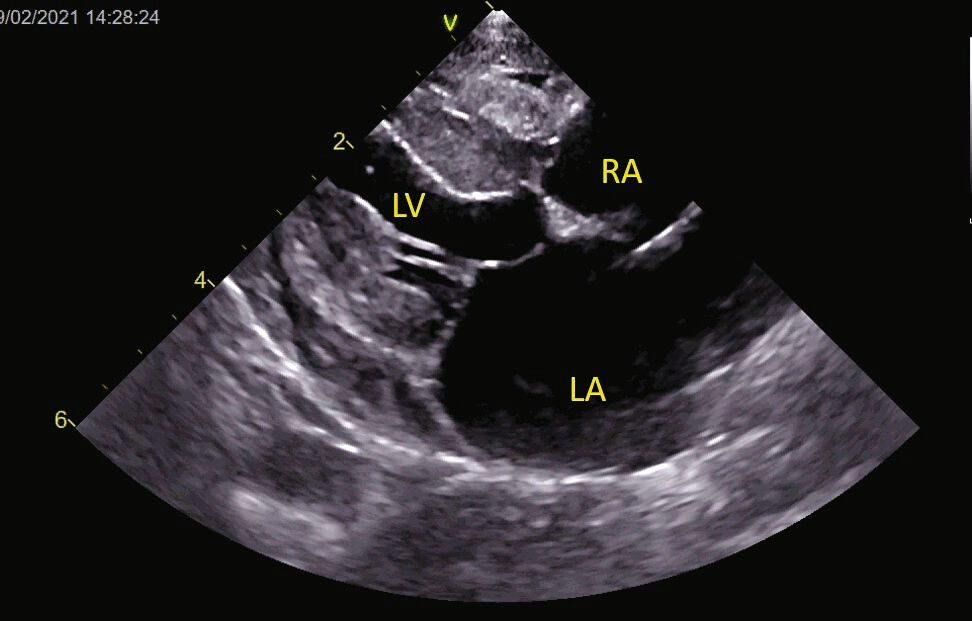

4. Cardiomyopathie dilatée (CMD) [2]. Autrefois associée à une carence en taurine, elle est aujourd’hui devenue rare, mais les cas actuels peuvent être liés à un problème génétique ou nutritionnel (par exemple, les régimes sans céréales). L’échocardiographie peut montrer une dilatation du VG en systole (> 12 mm) et en diastole (> 18 mm), avec une paroi relativement mince. Ce tableau peut également être observé au stade terminal d’autres cardiomyopathies (Figure 7).

Vue PSD (grand axe, 4 cavités) d’un Chat Européen présentant un tableau clinique de CMD

Figure 7a. Vue PSD (grand axe, 4 cavits) dun Chat Europen prsentant un tableau clinique de CMD. Le VG est arrondi, dilat et hypokintique ; le septum interventriculaire semble plus fin que la paroi libre du VG. Ces images peuvent illustrer le stade terminal dune autre cardiomyopathie. Catheryn Partington Joanna Dukes-McEwan